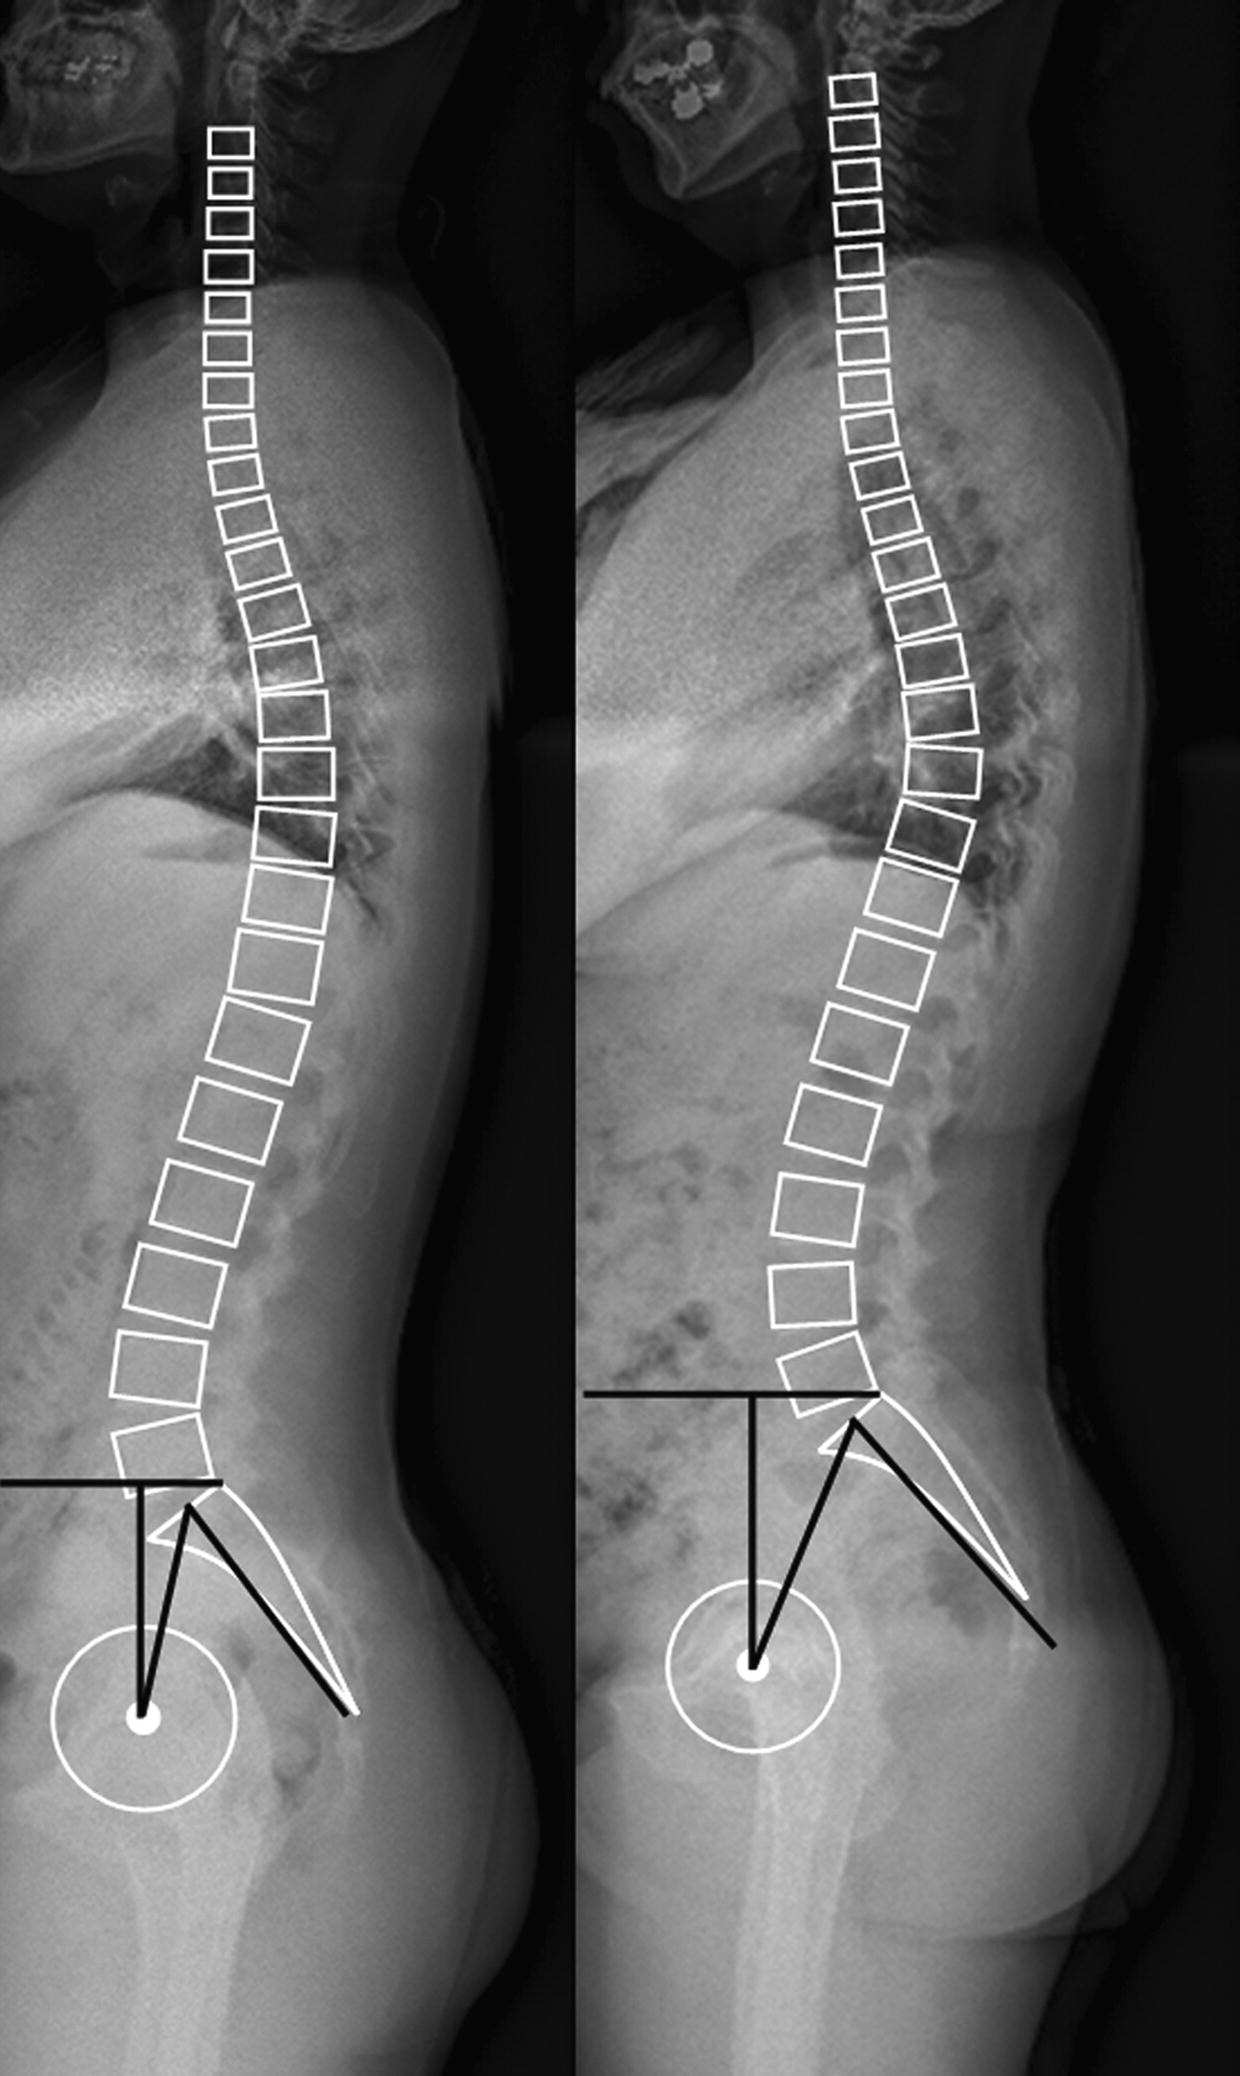

아래와 같이 고관절은 뒤쪽으로 서게 되는 자세로 어깨를 피고 무릎을 굽히는 등 다른 것으로 척추의 후만변형을 보상하려고 하는 자세입니다. 뒤뚱뒤뚱 걸으시는 할머니들을 생각하시면 될 것 같습니다.

Vertical sacrum 처럼 Sacral slope 이 감소하게되고

Lumbar lordosis가 감소하게 되며

Pelvic tilt 는 증가하게 됩니다.